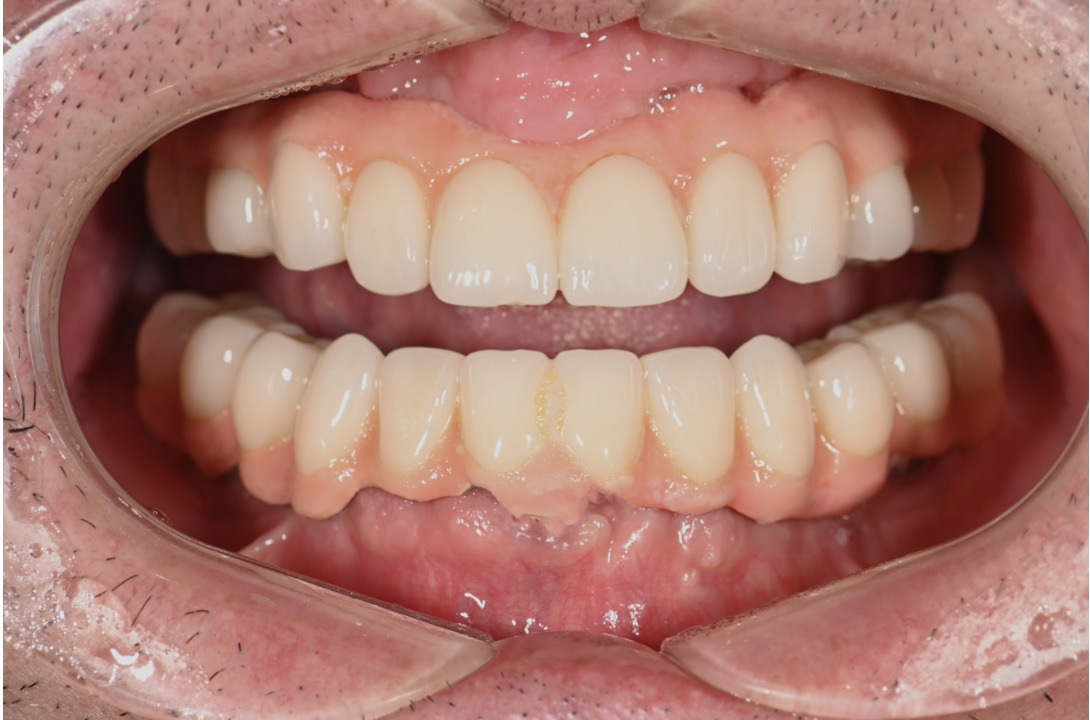

| 主訴 | 全体的にきれいにしたい |

|---|---|

| 治療内容 | 午前中に上下顎共に重度の歯周病、虫歯のため全ての歯を抜歯させていただき下顎はインプラントの土台を3本埋入し歯型を取り午後に上部構造(下顎全ての歯)を装着、上顎は一度総入れ歯を装着させていただきました。 治療が1日で完了しその日のうちに噛めるようになります。 |

| 治療期間 | 2回(1回目に資料取りをさせていただき2回目に下記の全ての治療をさせていただきました。) |

| 治療費 | 250万円 |

| 治療 リスク | 抜歯した部位などに関しては当日痛みが出ますので痛み止めなどを処方させていただきます |